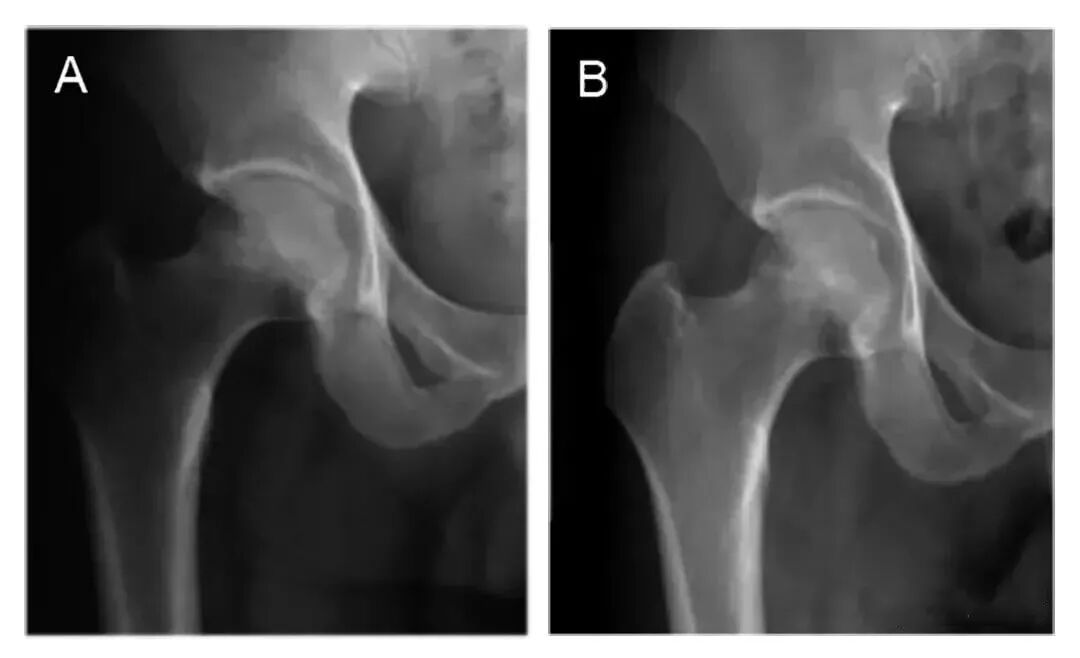

图中A和C:典型病例术前正位和蛙式位X射线片,

股骨头内不规则高密度影;

图B和D:典型病例术后7年正位和蛙式位X射线片,

股骨头外形规整,无塌陷。